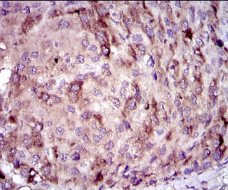

CRP Mouse Monoclonal antibody[1G1E8]

IHC    1/200 - 1/1000